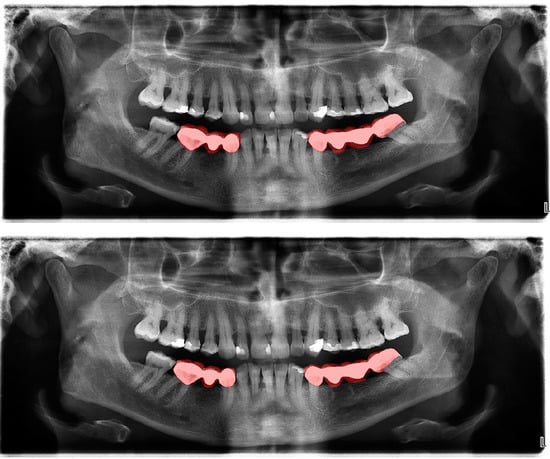

Figure 4.

Automatic segmentation of the bridges. Manual segmentation (upper image) and automatic segmentation (lower image) can be seen above.

In crown–bridge segmentations, several large amalgam fillings have been mi-segmented as crown restorations in some cases due to both their width and metallic opacities. To avoid this type of error, amalgam restorations and composite restorations can be segmented with separate labels, and more OPGs that have both amalgam restorations and crown–bridge restorations can be included into the dataset.